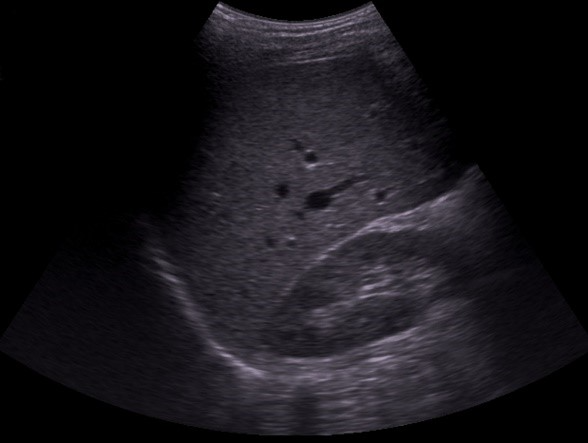

The Surgery Clerkship Ultrasound requirement consists of documentation of the presence or absence of free fluid in the chest, abdomen, and pelvis (FAST Scan) as well as a gallbladder image.

Right Upper Quadrant

Gallbladder